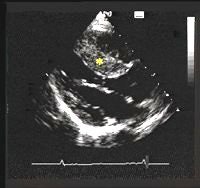

| HCM is the most common cause of sudden cardiac death in young athletes and people younger than 30 years of age. In a normal heart, the heart walls are 11 mm or less in thickness (above and below). |

| Patients with HCM have a characteristic thickening of the heart walls that can range from 14-60 mm. Particular thickening of one part of the heart, the interventricular septum, is characteristic of patients with HCM. The thick interventricular septum is marked with an asterisk. Images courtesy of the Hypertrophic Cardiomyopathy Program, St. Luke's-Roosevelt Hospital Center, New York City. |